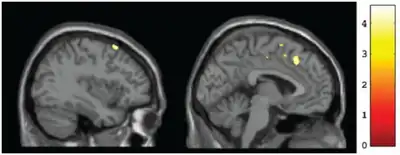

Sagital views of grey matter (left) CT v. (right) Fetal alcohol spectrum disorder (yellow markings depict clusters)